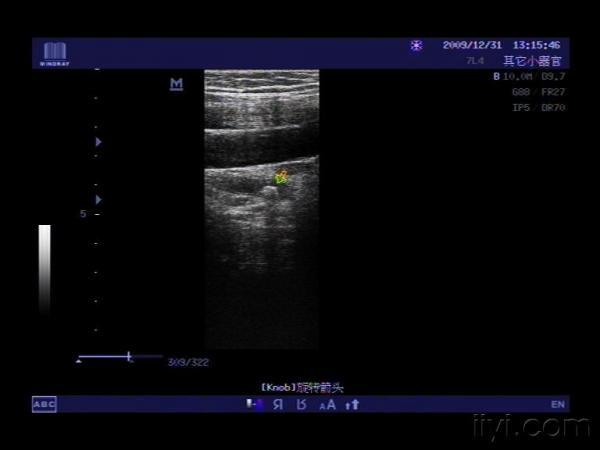

输尿管结石 - 超声医学讨论版 - 爱爱医医学论坛 - 医

输尿管结石腹部探头和高频探头图像对照 - 超声医学版

清楚的输尿管结石 - 超声医学讨论版 - 爱爱医医学

输尿管结石

超声图像